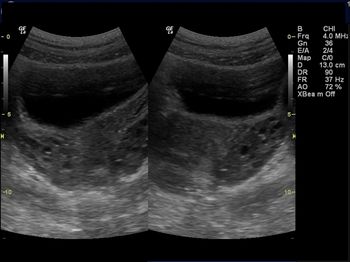

Challenge your diagnostic skills: What is the cause of this young woman’s irregular menses?

What is your diagnosis based on these images from a young woman with irregular menses?